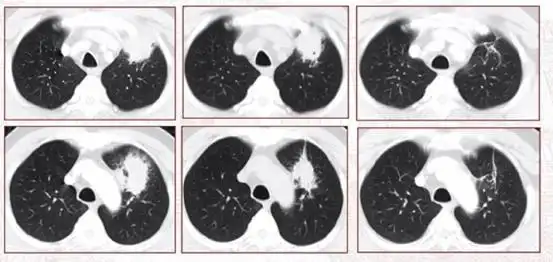

正常,结核肺的图片

感染肺结核后多久拍ct能发现?还有什么判断途经?听医生解答